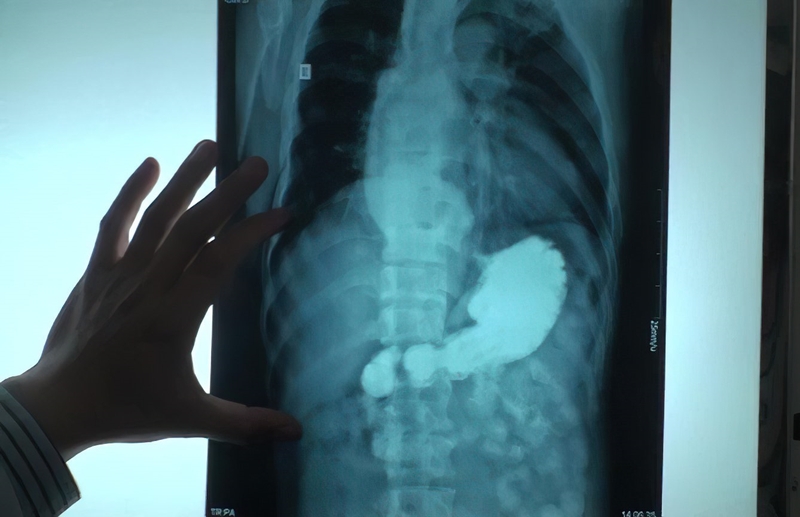

Chụp X quang dạ dày là một kỹ thuật chẩn đoán hình ảnh quan trọng và được áp dụng phổ biến để phát hiện, theo dõi các bệnh lý liên quan đến dạ dày. Để thực hiện kỹ thuật này cần có máy chụp X quang có thể phát ra các tia X - các tia bức xạ năng lượng cao. Tia X được phát ra máy chụp có thể đi xuyên qua cơ thể của chúng ta. Khi nó đi xuyên qua vùng bụng chứa dạ dày, tia X sẽ tiếp tục đi đến phim X quang có vai trò là tấm thu nhận hình ảnh Lúc này, hình ảnh dạ dày và các cấu trúc khác bên trong khoang bụng của người bệnh sẽ được hiển thị trên phim chụp X quang.

Khác với chụp X quang thông thường, chụp X quang dạ dày cần dùng thuốc cản quang. Thuốc cản quang (barium) là một loại muối kim loại, không bị nước hay các dung môi hữu cơ hòa tan nên khá an toàn với sức khỏe. Khi người bệnh dùng thuốc cản quang, những tổn thương tại thực quản, dạ dày, tá tràng của người bệnh sẽ được hiển thị rõ hơn trên phim chụp. Điều này giúp các bác sĩ có thể quan sát dễ dàng và đưa ra những chẩn đoán bệnh chính xác hơn. Chụp X quang có ảnh hưởng gì không? Về cơ bản, đây là kỹ thuật chẩn đoán hình ảnh an toàn, ít tác dụng phụ và không xâm lấn.